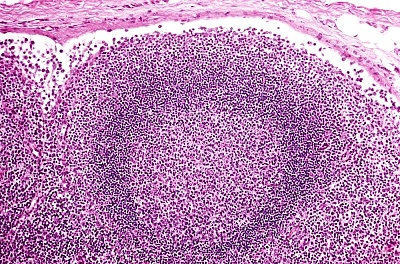

无色素痣又称脱色素痣,出生时或生后不久发病,损害往往沿神经节段分布,表现为局限性或泛发性减色斑,境界模糊,边缘多呈锯齿状,周围几无色素增殖晕,有时其内混有淡褐色粟粒至扁豆大小雀斑样斑点,感觉正常,持续终身不变。